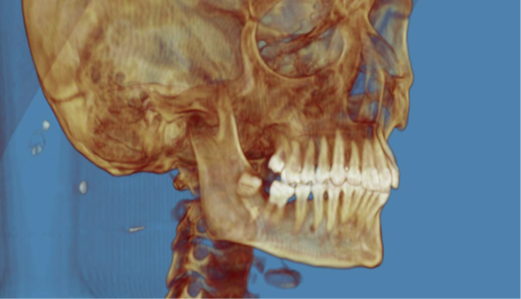

Bilateral Comminuted Mandibular Fracture Caused by Gunshot Wound: Case Report Using Prototyping to Assist Surgical Planning

Julia Tavares Palmeira, Diego Learth Lima, Ricardo Franklin Gondim, José Maria Sampaio Menezes Junior, Clarice Maia Soares de Alcântara Pinto